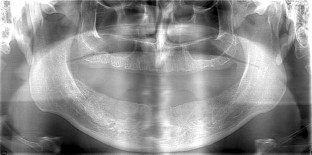

Fig. 2